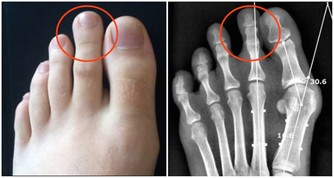

鞣質確實會與胃酸、果肉蛋白髮生作用,形成膠凍樣的物質。在胃消化食物不那麼順利的情況下,是導致胃結石的導火索。這個病不但治療麻煩、而且會導致胃潰瘍甚至是大出血。